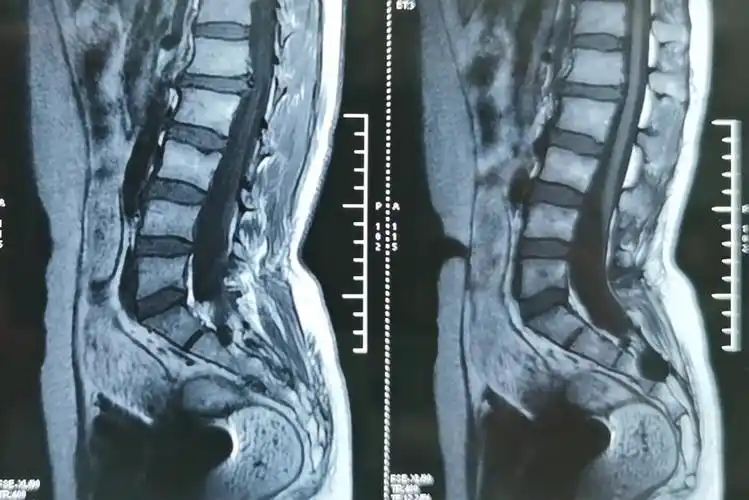

73-骶管囊肿(男性,43岁,腰痛4年)